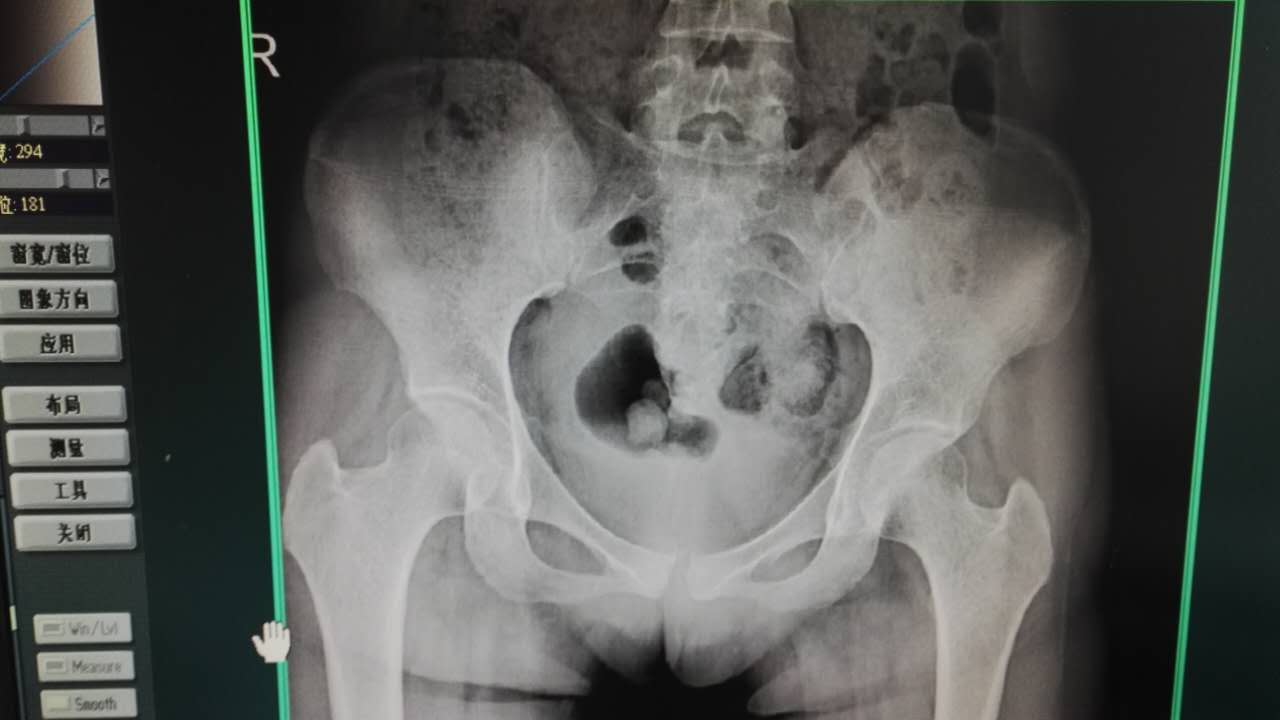

要知道,一般情况下,正常女性的耻骨联合处的间距大约为4~6mm,由韧带实现连接。等到怀孕之后,耻骨联合处之间的韧带也会随之变化,达到6~9mm左右。

当然,分娩结束以后,其中的韧带长度只会变得更长,且因为每个人的体质、宝宝的体型以及分娩过程中的情况都有所不同,导致耻骨联合处的韧带可能会发生不同变化,最后长度都会有所不同。

一部分症状较轻的女性,韧带长度不超过10mm,也就意味着骨盆、胯部不会有太大的变化,而超过10mm,就会影响到女性正常的生活状态,在女性如厕、走路、翻身等等动作时都会感觉到痛感。

针对这种情况,一般是建议保守治疗,不采取较为特殊的治疗方式。但如果韧带长度超过25mm,那么就需要通过手术治疗了。当然,新妈妈们也不要过于担心,毕竟出现这一种情况的几率较小,不到1%。